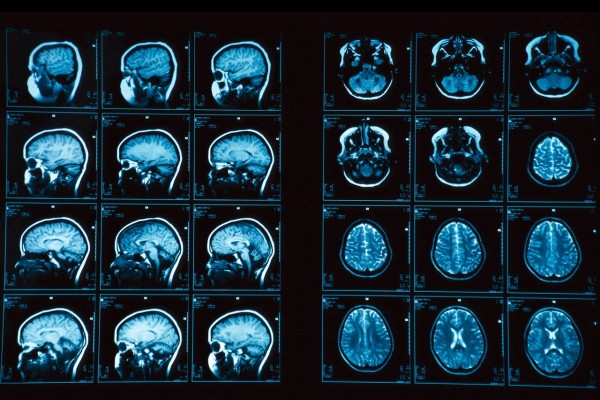

Международная группа ученых проанализировала образцы ДНК и результаты сканирования мозга более чем 1500 подростков, а также провела серию тестов для определения коэффициента их вербального и невербального интеллекта.

Ученых интересовала, в первую очередь, толщина коры головного мозга испытуемых, так называемой «серой материи», которая играет ключевую роль в развитии памяти, уровня внимания и восприятия, мышления и совести.

Затем были проанализированы десятки тысяч (более 54 000) генетических вариантов, которые могли оказать влияние на процесс развития мозга. При этом удалось доказать, что у подростков с определенными генами кора в левом полушарии головного мозга была тоньше. Именно они показали наихудшие результаты в тестах IQ.